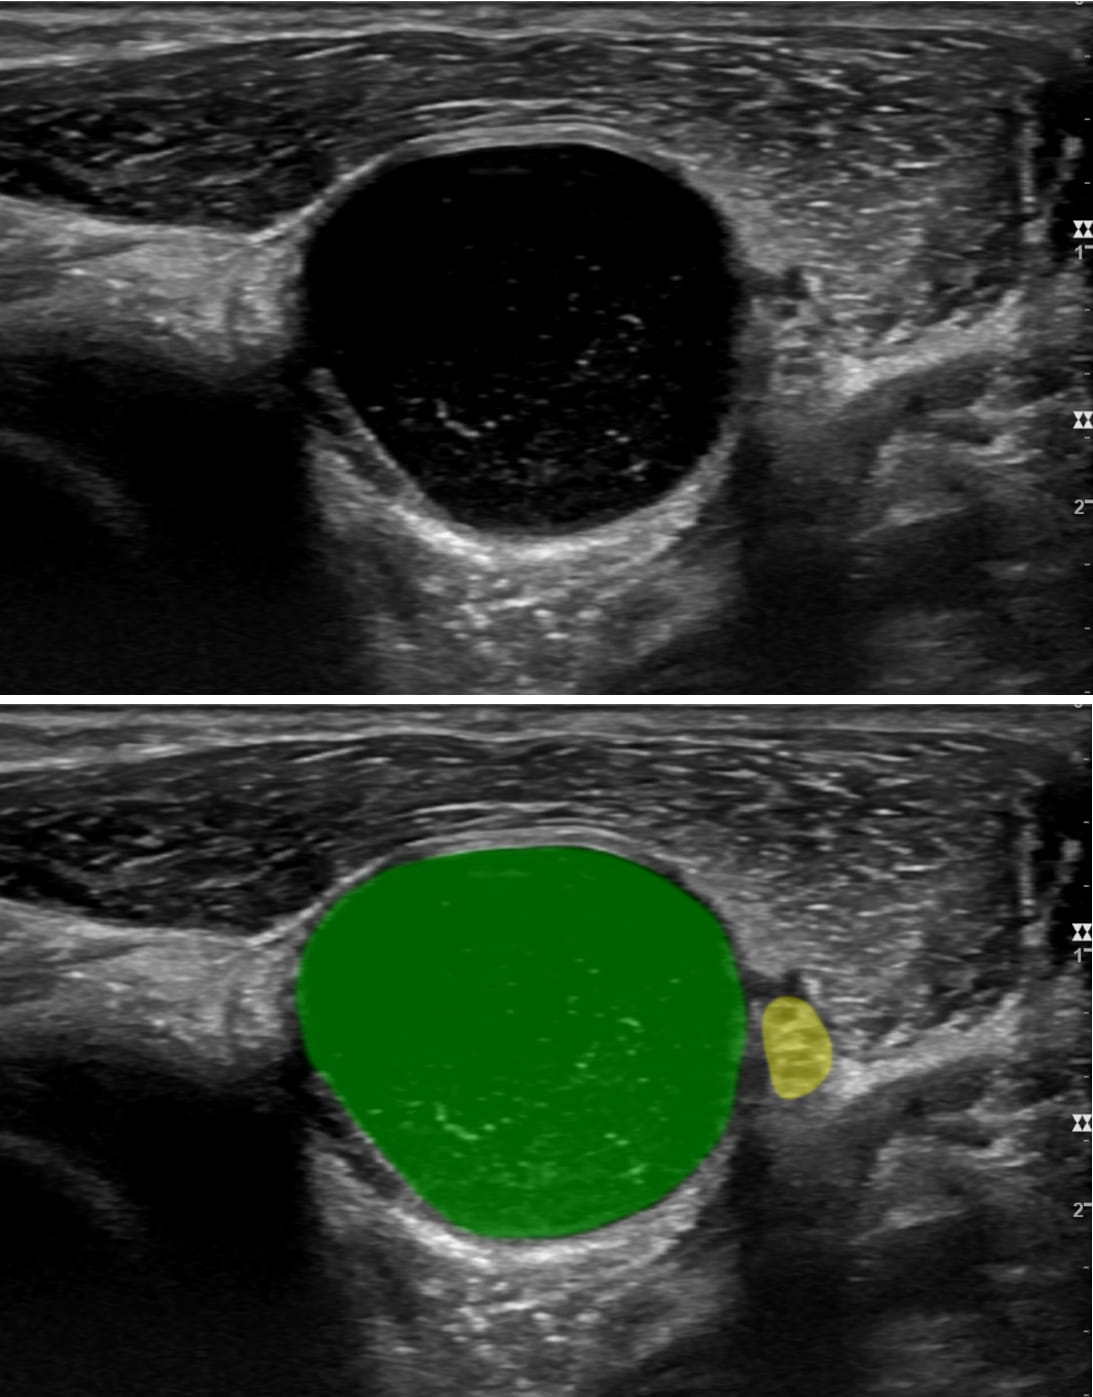

In another case, a woman presented with a complete wrist drop that emerged upon waking in the morning. She was unable to lift her fingers and had numbness of the back of her hand. An EMG study indicated that it was likely from compression, perhaps due to sleeping on it in an awkward position, a problem that would normally resolve on its own. However, a subsequent ultrasound identified a large synovial ganglion cyst in her upper arm, which was removed without delay.

Image Caption: A large ganglion cyst (green) is displacing the radial nerve (yellow)  near the elbow. Image Caption: A large ganglion cyst (green) is displacing the radial nerve (yellow) near the elbow. Patient awoke with marked weakness of wrist and finger extensors. Clinically, she had a radial nerve lesion. The thought was this was external compression and she must have “slept on it funny.” The ultrasound demonstrated that it was actually a large ganglion cyst compressing the radial nerve. This was then surgically corrected.